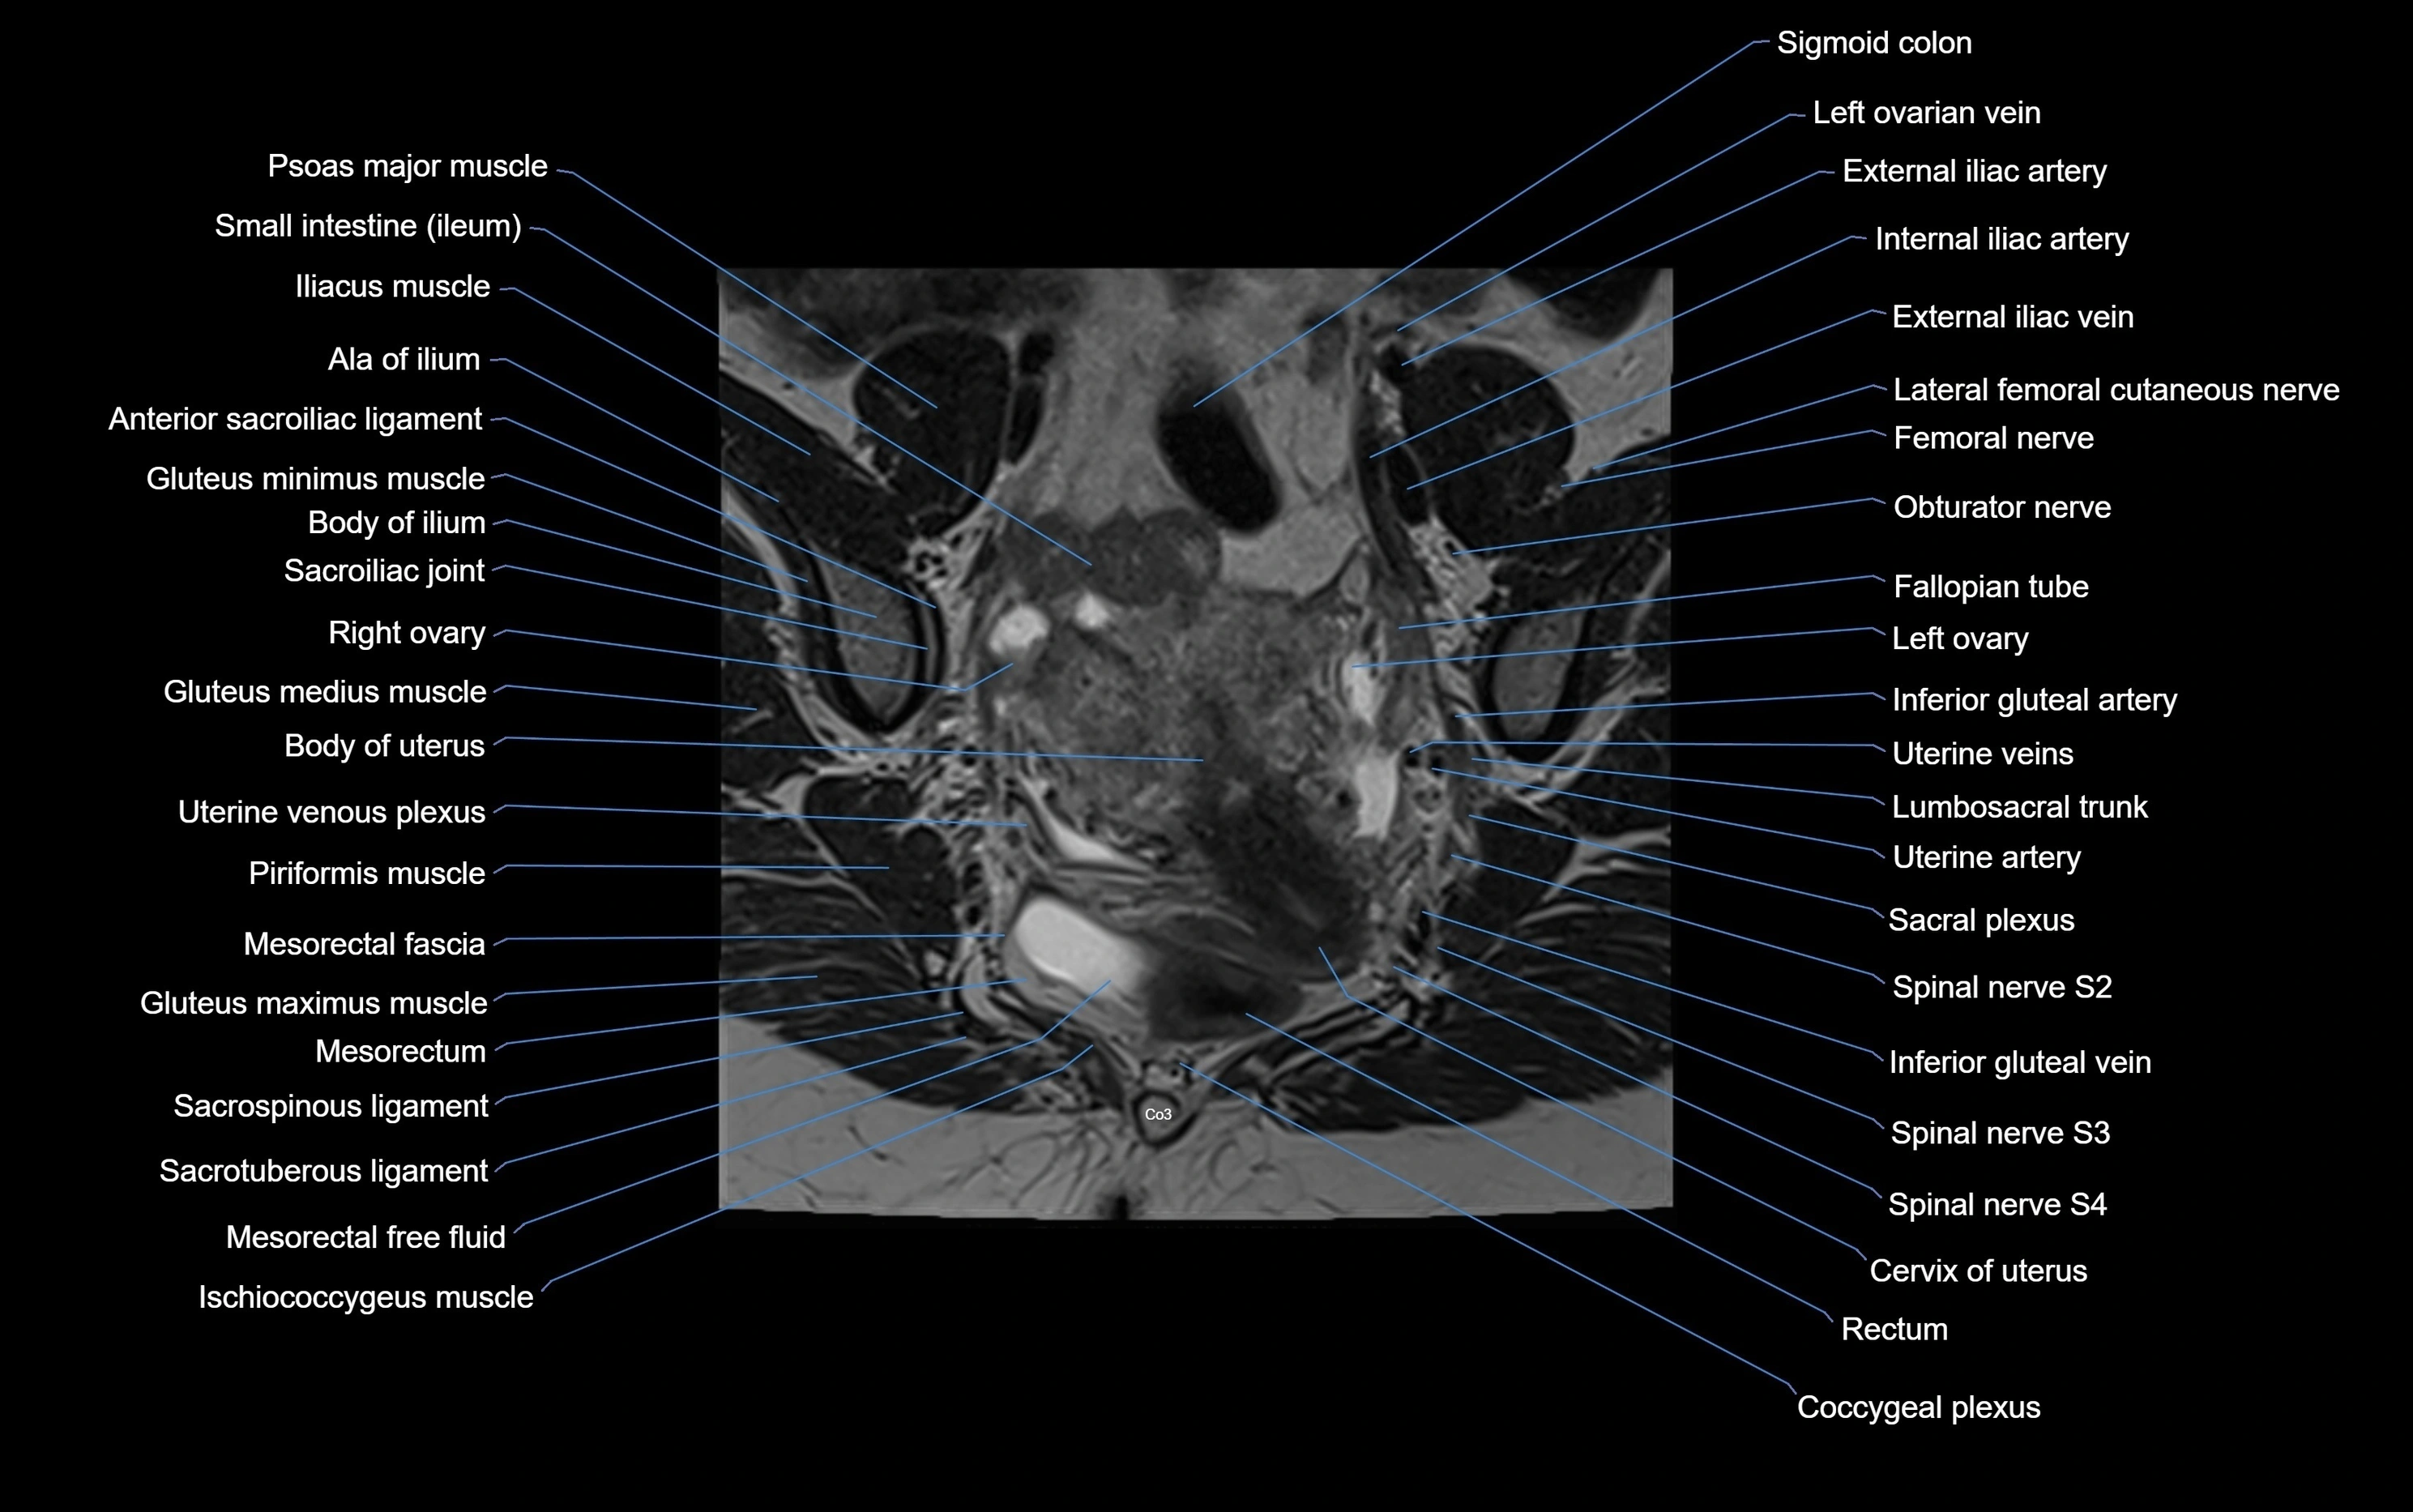

CT VRT image

image